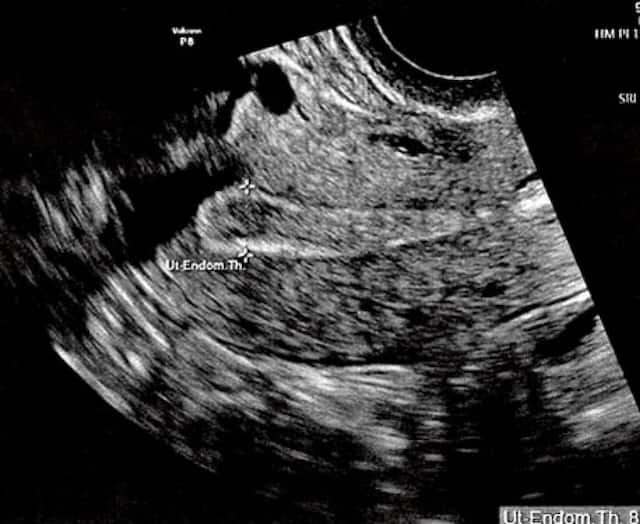

CONCEPTION’S PERFECT TIMING

After in vitro fertilization, Carolyn Bilson holds up her ultrasound marked “G.L.” for good luck by Ilan Tur-Kaspa (in blue), the medical director of the Institute for Human Reproduction in Chicago. Bilson and her partner, Tim O’Brien, conceived Westley (below) with personalized embryo transfer.

COURTESY BILSON/O’BRIEN FAMILY

Top: The ultrasound image of Bilson’s uterus shows her endometrial lining is 8.9 millimeters thick, usually enough for implantation. But the genetic testing… Read More

Westley was conceived with personalized embryo transfer. Tur-Kaspa sampled 238 genes from Bilson’s uterus to determine when she would be most receptive to implantation. An interim study found a 24 percent rise in IVF pregnancy rates with this method.